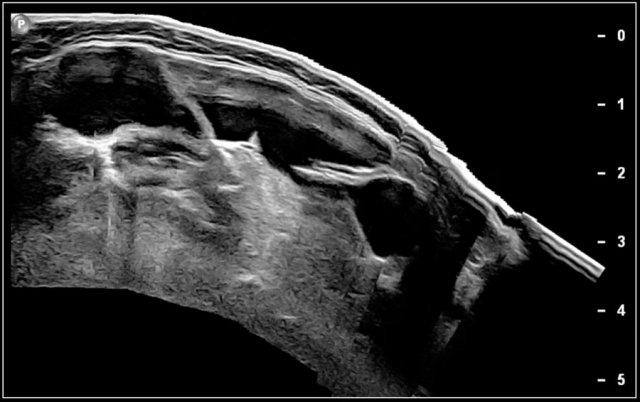

Video cho thấy một khối sưng xuất hiện qua đêm ở một bé gái 13 tuổi.

Một tổn thương giảm âm được nhìn thấy nằm nông so với động mạch cảnh và sâu so với cơ ức đòn chũm.

Không thấy sự di chuyển của nội dung tổn thương khi gõ nhẹ bằng đầu dò.

Khi bé gái được yêu cầu ngồi thẳng, nội dung bên trong xoáy chuyển động.